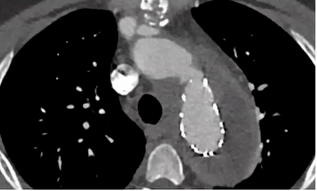

2)症状不典型agi,病例为复合手术后股动脉切口愈合不良,胸痛,无发热